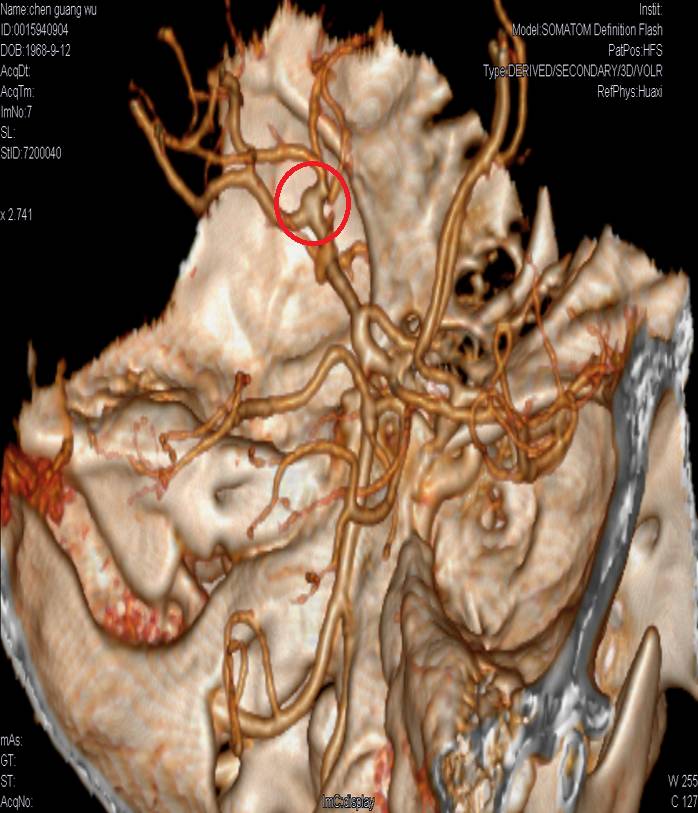

DSA:基底动脉尖端分叶状小动脉瘤,左侧颈内动脉床突上段动脉瘤。

颈内动脉床突段一约3.5mmx2.75mm囊性显影,动脉瘤。

基底动脉尖1.8mmx3.2mm囊性显影,分叶状动脉瘤。